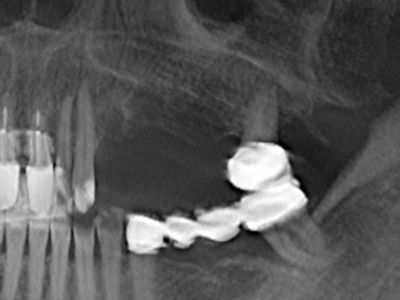

Abb. 11: Das postoperative OPTG veranschaulicht die vertikale Augmentation und Sinusbodenelevation.

Abb. 15: Die röntgenologische Ein-Jahres-Kontrolle zeigt stabile Verhältnisse des Knochenniveaus.

Bei der Knochenblockentnahme zeigen sich weitere Vorteile für die Piezochirurgie: Neben der bereits beschriebenen hohen Präzision bei der Osteotomie stellt sich gerade die Verwendung der dünnen Sägespitzen als besonders materialschonend heraus. Bei der Verwendung insbesondere von Lindemannfräsen sind mit deutlich höheren Entnahmeverlusten durch die dickere Instrumentenspitze zu rechnen (Lakshmiganthan, Gokulanathan et al. 2012). Die insbesondere bei retromolar entnommenen Blocktransplantaten notwendige basale Abtrennung wird durch speziell hierfür vorgesehene rechtwinklige Sägen erleichtert, so dass die Piezochirurgie als präzises, übersichtliches und sicheres Verfahren zur retromolaren Knochenblockgewinnung angesehen wird (Happe 2007) (Abb. 1-12).

Knochengewebe ist nicht nur rein mineralisch, sondern auch in wesentlichen Anteilen aus Kollagenfasern aufgebaut. Dies gewährleistet neben einer guten Druckfestigkeit eine gewisse Flexibilität, welche für die Durchführung von Augmentationen genutzt werden kann. Bei der klassischen Expansionsplastik im Sinne eines Bone Splittings wird der atrophierte Kieferkamm in seiner Längsachse gespalten und nach Erreichen einer ausreichenden Osteotomietiefe vorsichtig aufgedehnt (Abb. 13-16), idealerweise ohne den Kiefer wesentlich zu deperiostieren (Brugnami, Caiazzo et al. 2014, Stricker, Fleiner et al. 2014). Bewährt haben sich Schrauben- und Plattensysteme mit zunehmender Expansionsdistanz, um die beiden Knochenlamellen unterhalb der Bruchschwelle voneinander zu distanzieren. In der Regel werden Restknochenbreiten von mindestens 3-4 mm gefordert (Chiapasco, Zaniboni et al. 2006), um eine ausreichende Flexibilität und knöcherne Bedeckung der einzubringenden Implantate zu gewährleisten. Ggf. kann eine ein- oder beidseitige vertikale Entlastungsosteotomie die Flexibilität verbessern. Als Alternative zur klassischen Technik wurde eine Kombination mit weiteren augmentativen Techniken vor allem auf der bukkalen Seite beschrieben.